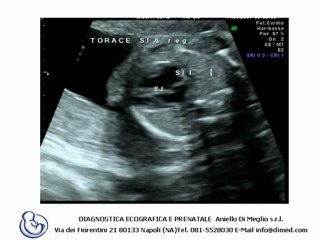

Aneurisma dell'arco aortico, a Modena protesi mai vista in Italia